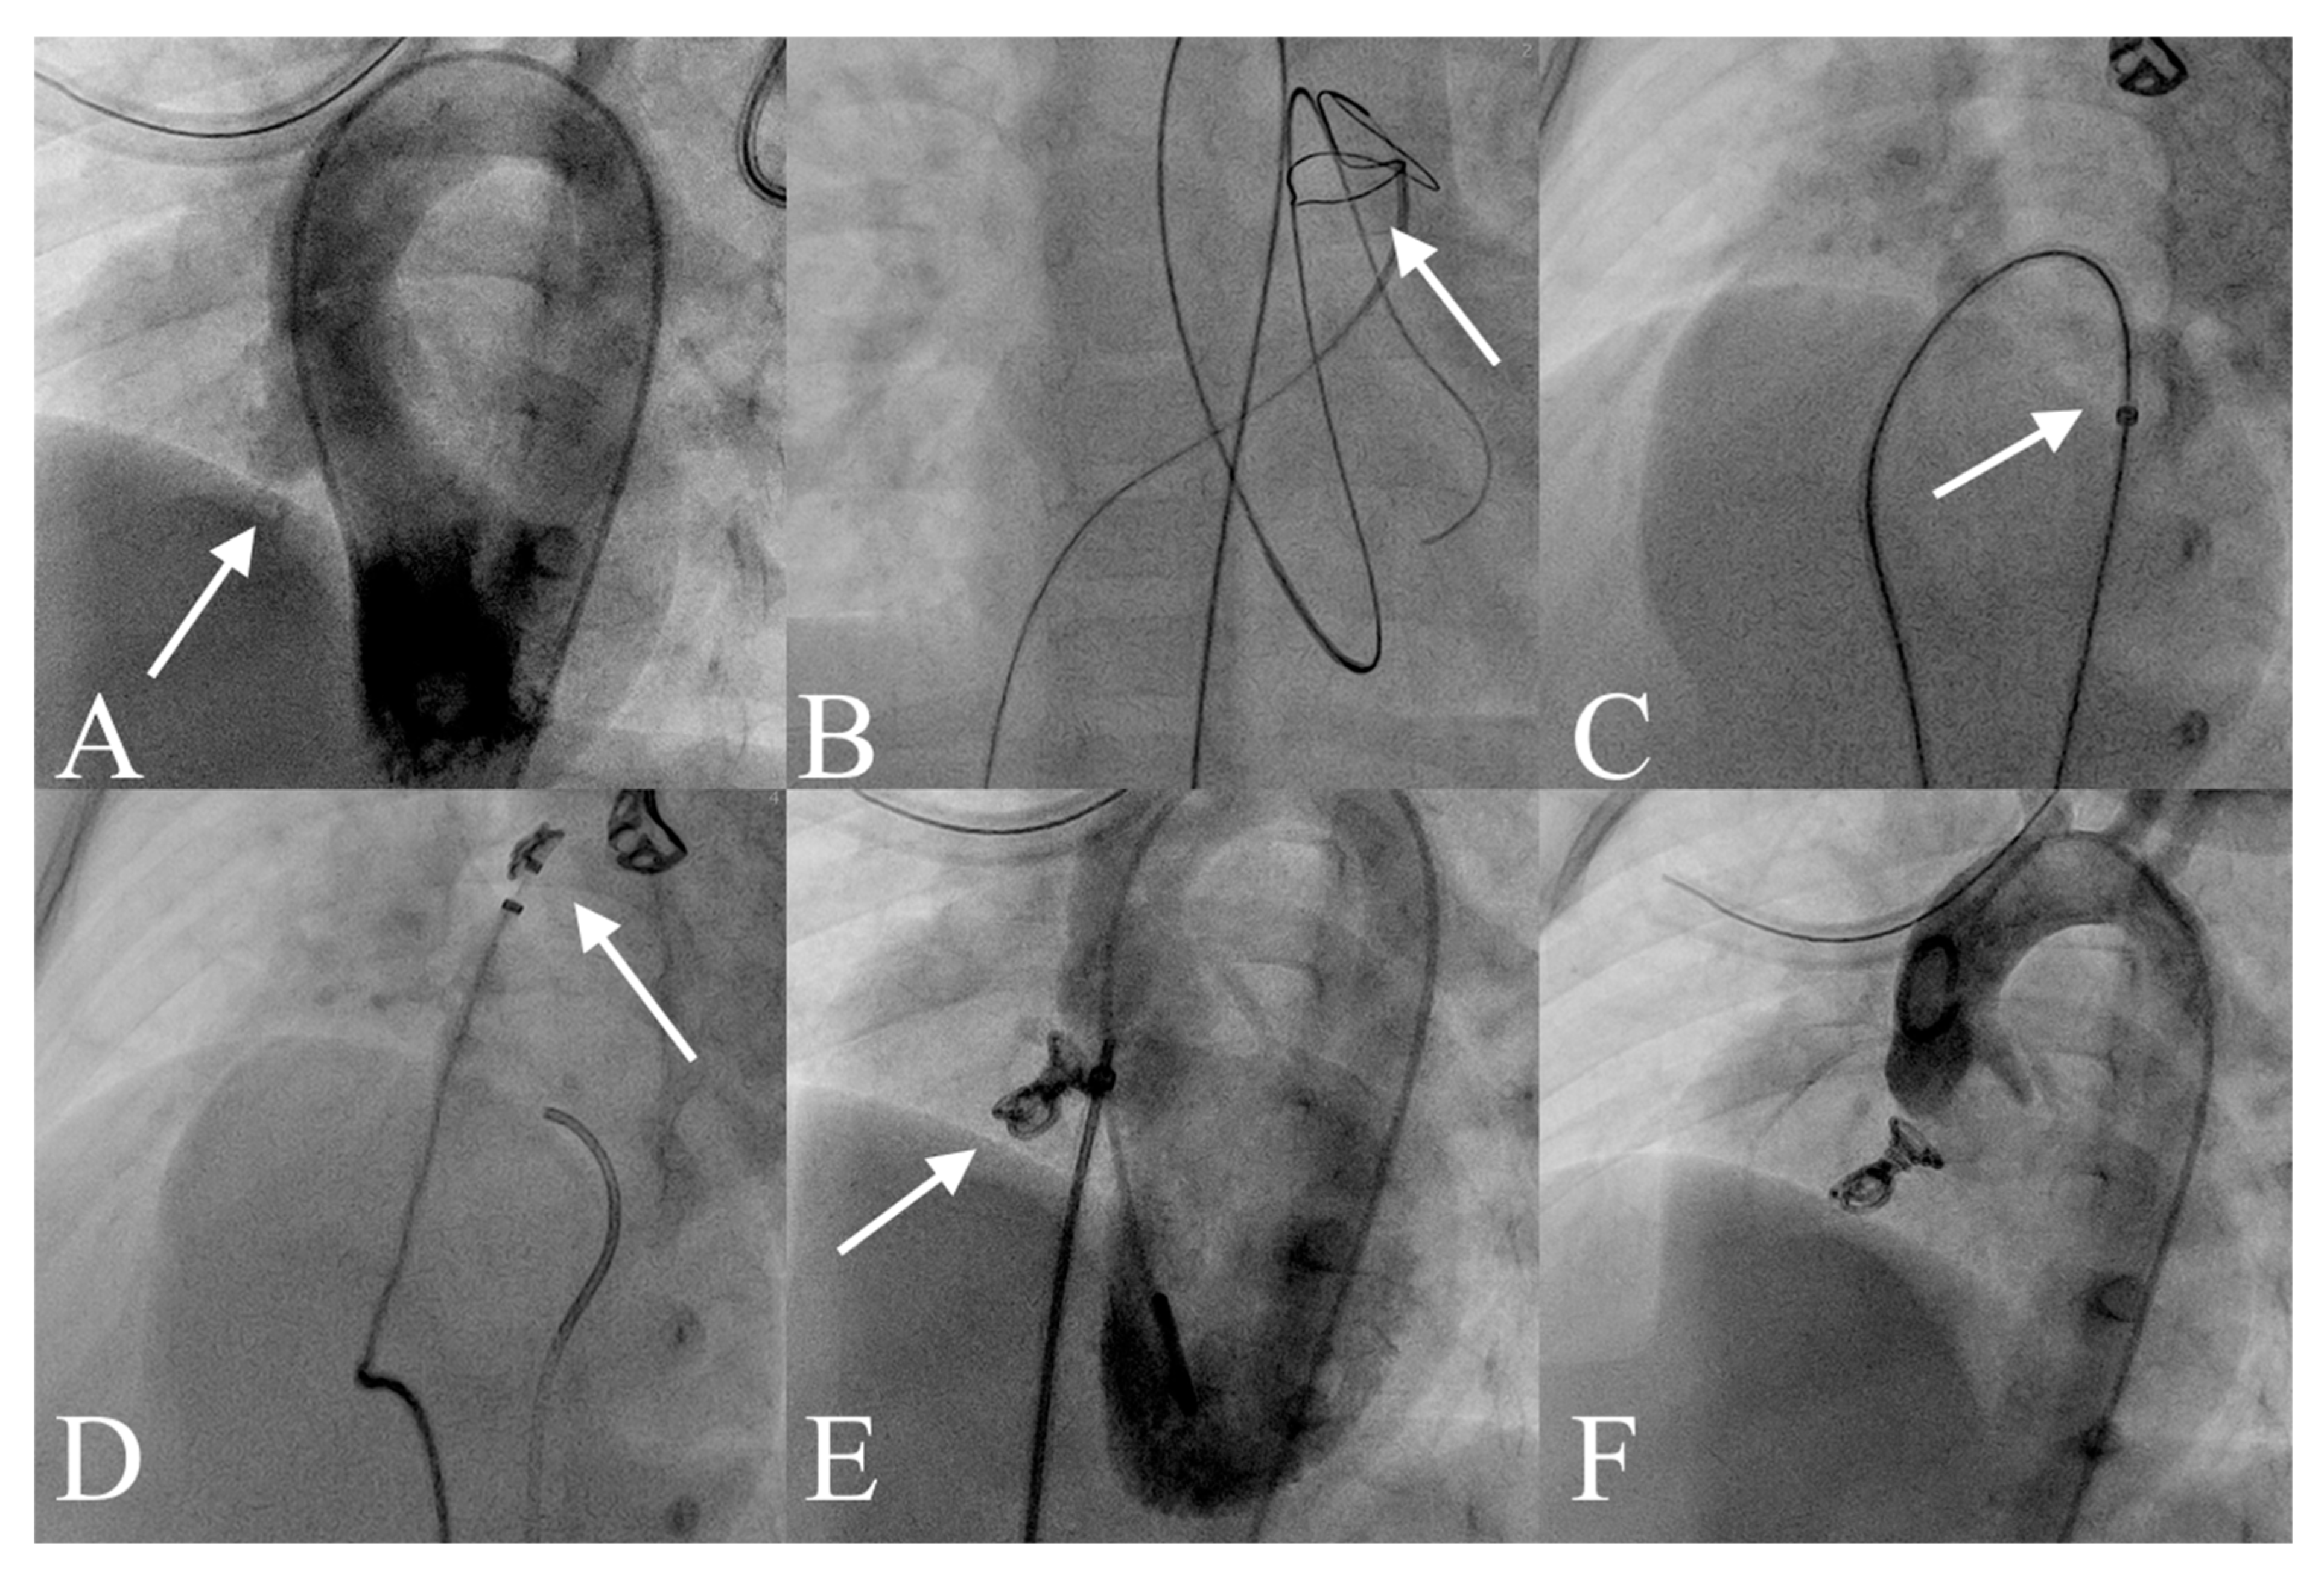

2.3. VSD Closure Protocol